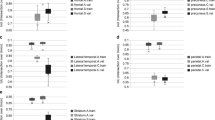

The Dice coefficients of the deep learning methods based on MPRAGE, Dixon, and mUTE images were 0.84 (0.91), 0.84 (0.92), and 0.87 (0.94) for the whole-brain (above-eye) bone regions, respectively, higher than the atlas method of 0.52 (0.64). The regional SUVR error for the atlas method was around 6%, higher than the regional SUV error. The regional SUV and SUVR errors for all deep learning methods were below 2%, with mUTE-based deep learning method performing the best. As for the surface analysis, the atlas method showed the largest error (> 10%) near vertices inside superior frontal, lateral occipital, superior parietal, and inferior temporal cortices. The mUTE-based deep learning method resulted in the least number of regions with error higher than 1%, with the largest error (> 5%) showing up near the inferior temporal and medial orbitofrontal cortices.